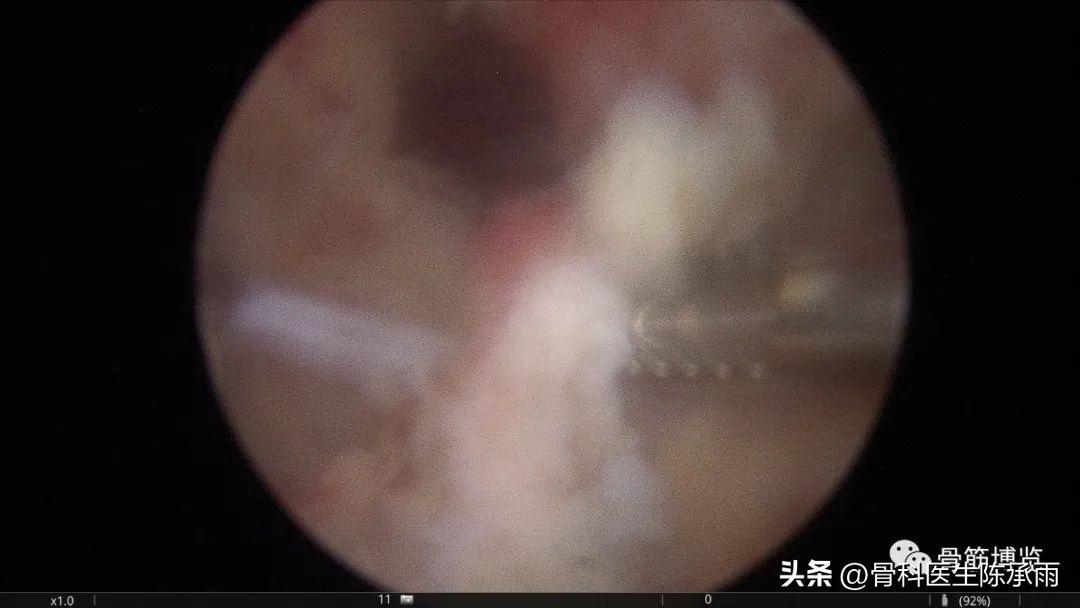

术中情况:关节破坏严重

关节清理结束后内侧脓肿小切开引流,VSD负压持续吸引,外侧置管持续庆大生理盐水冲洗。